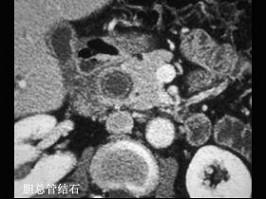

胆总管结石与胰头癌的主要鉴别特点是 ( )A、有无皮肤瘙痒B、有无肝功能改变C、有无淀粉酶改变D、有无肿大胆囊E、有无进行性黄疸

问题 胆总管结石与胰头癌的主要鉴别特点是 ( )

选项 A、有无皮肤瘙痒 B、有无肝功能改变 C、有无淀粉酶改变 D、有无肿大胆囊 E、有无进行性黄疸

答案 E